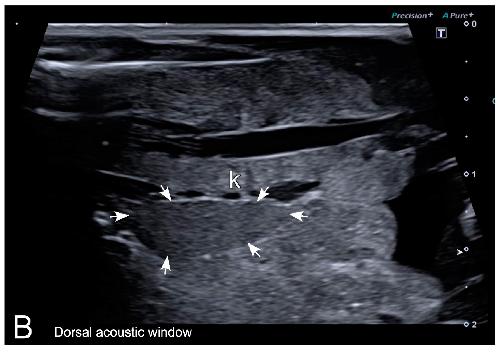

Figure 7. Representative HR-US images of Kaloula pulchra (A) and Xenopus laevis (B) males obtained in the longitudinal plane using a dorsal acoustic window. The testes (delimited by arrows) appeared as structures with oval morphology, mid echogenicity and homogenous echotexture. Testes were located just ventral or ventrolateral of the ipsilateral kidney (k).